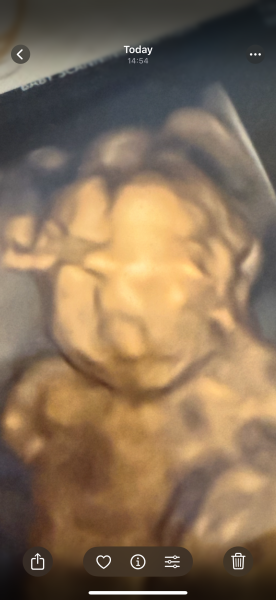

Does this look like a cleft palate?

Had a private wellbeing scan today and they took this 4D scan. I’m 16 weeks so appreciate it still has a lot of developing to do but wondering if it looks like a cleft palate

At the stage you're at everything is still developing so they really do look like a little alien. They'll look for a cleft palate at the 20 week scan, which is much more accurate. Try not to worry.

To be pedantic, they will look for a cleft lip at the 20 week scan, not a cleft palate.

Cleft palates are very difficult to see on a scan and so are generally diagnosed after birth.

I would think if your private scan had suspected a cleft lip, they would have said something. Please try not to worry.